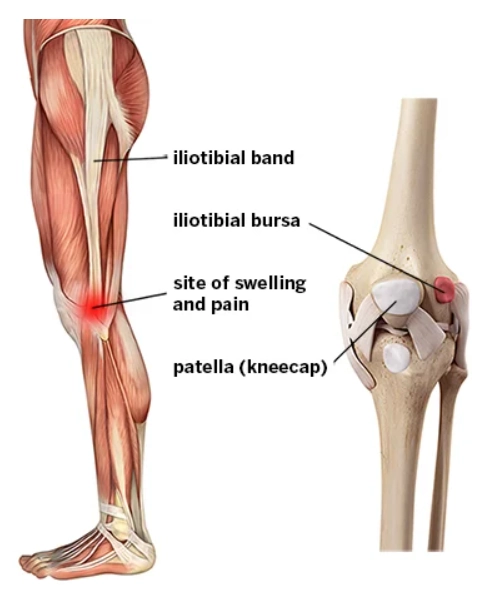

Hội chứng dải chậu chày (Iliotibial band syndrome)